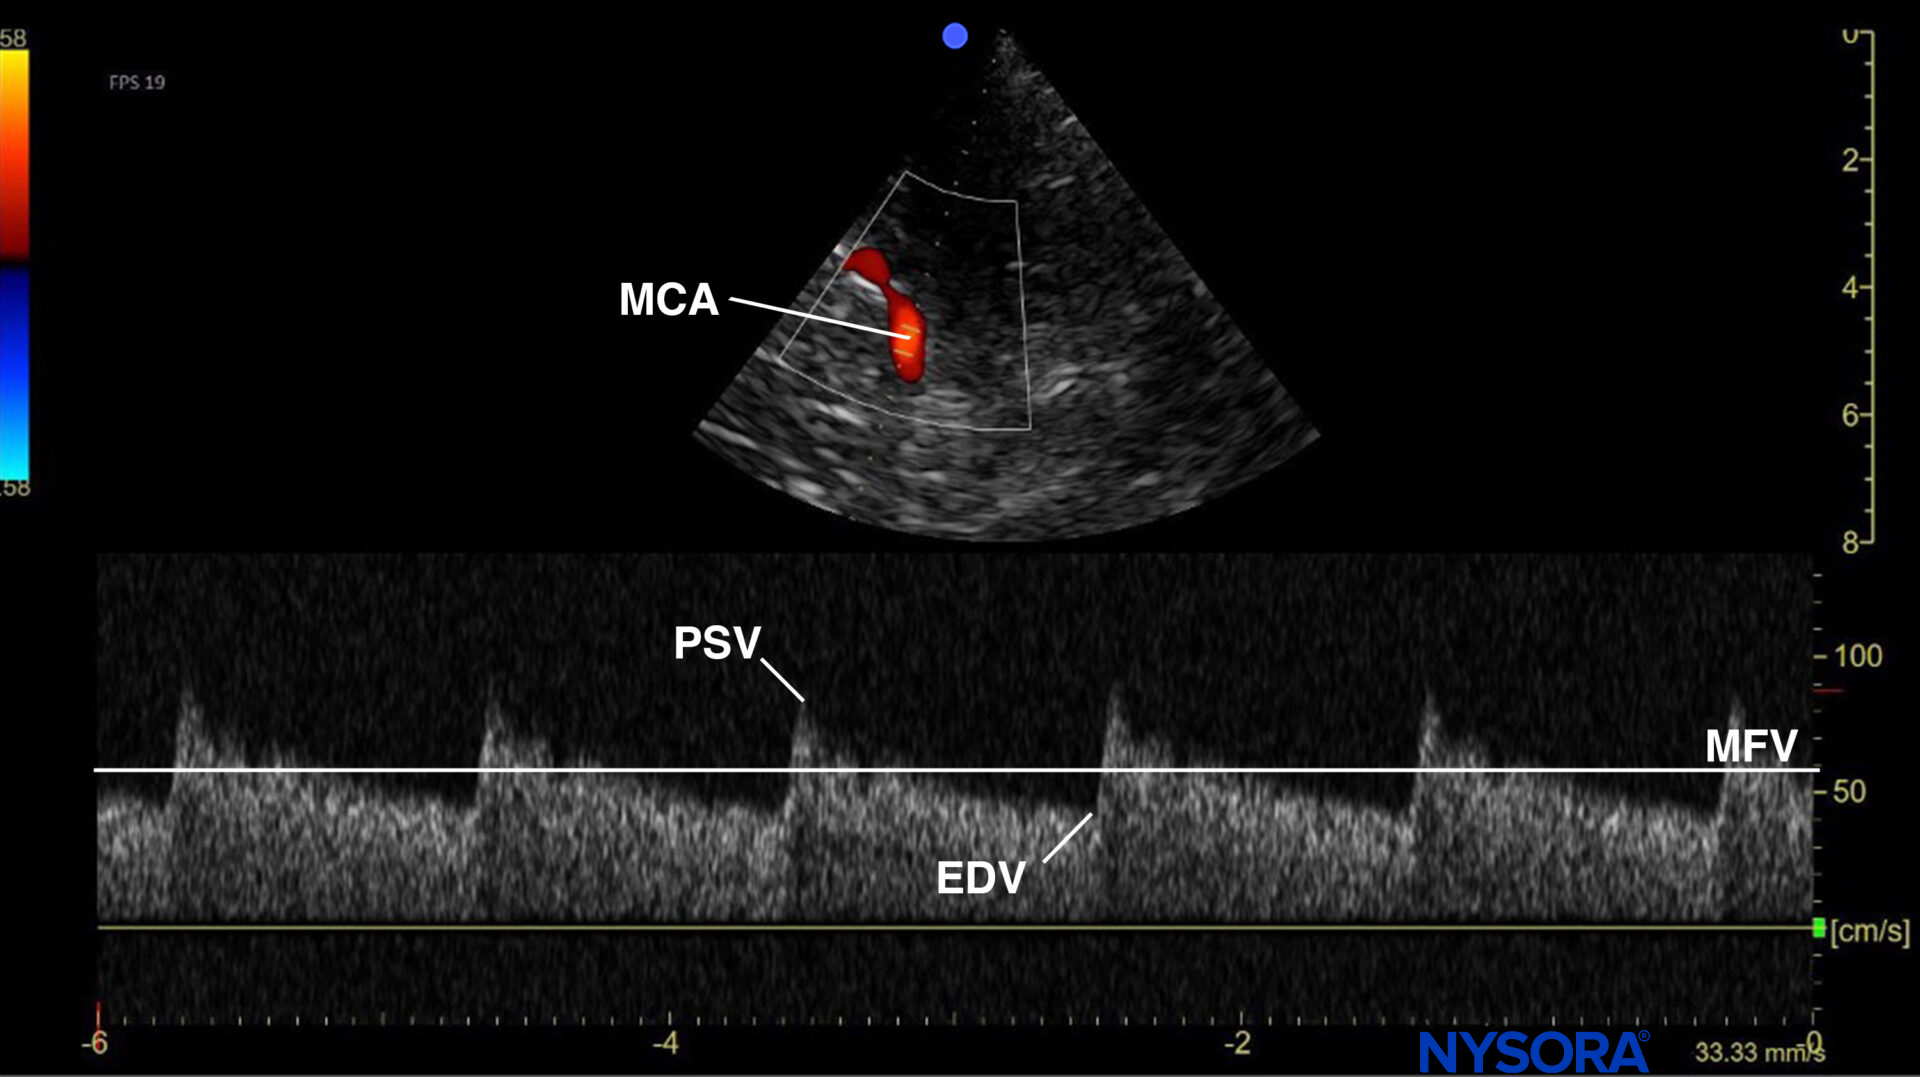

Use the mesencephalic plane and activate pulsed wave Doppler. Position the Doppler gate on the middle cerebral artery (MCA) and trace the flow velocities.

Mesencephalic plane pulsed wave Doppler with the Doppler gate on the middle cerebral artery (MCA). Evaluation of flow velocities in the MCA. PSV, peak systolic velocity; EDV, end-diastolic velocity; MFV, mean flow velocity.

Increased intracranial pressure (ICP) will affect cerebral blood vessel resistance and, consequently, cerebral blood flow velocities. Detection of a high resistance waveform or a high pulsatility index (PI) (= Gosling index) suggests a raised ICP. The pulsatility index equals the peak systolic velocity (PSV) minus the end diastolic velocity (EDV) divided by the mean flow velocity (MFV).

Middle cerebral artery flow velocity over time. PSV, peak systolic velocity; EDV, end-diastolic velocity; MFV, mean flow velocity.

PI = (PSV – EDV)/ MFV

- A normal PI usually ranges between 0.5 and 1.

- A PI > 1.2 should raise suspicion of increased intracranial pressure.